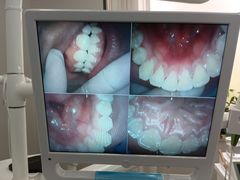

• 牙博士口腔品牌连锁(杨浦店)

• -牙博士口腔品牌连锁(杨浦店)

奶酪红烧桃子 | 22-08-09